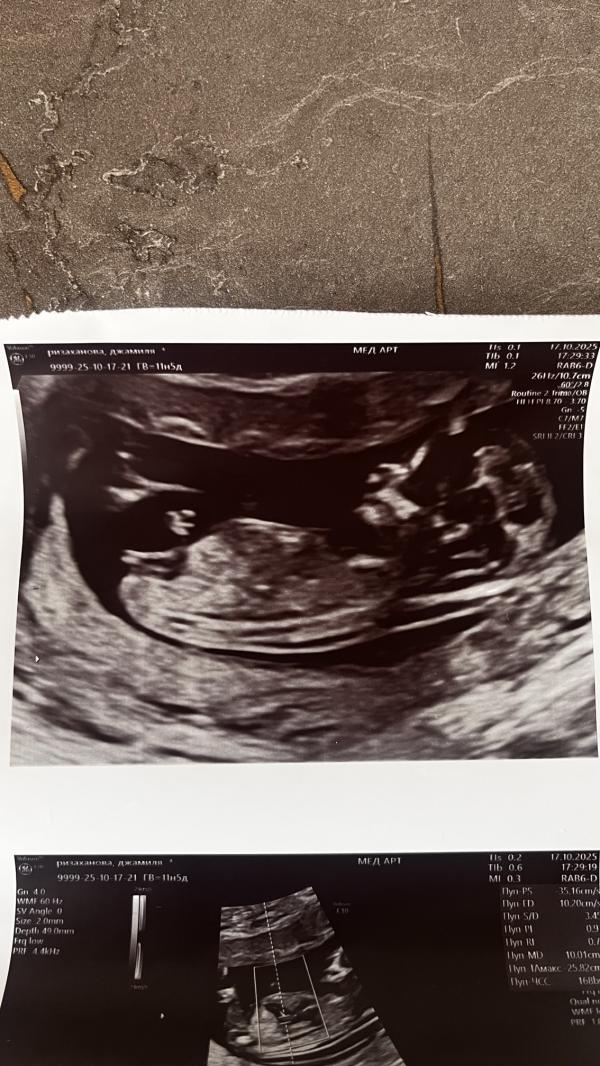

post image

Мальчик или девочка?

Бугорок смотрит вниз у мальчиков прям стоит 😸

@sanmarino, ой,тут не видно полового бугорка 🥹

У мальчиков половой орган наверх торчит а у девочки прямо как у вас, но срок маленький может ещё отрастет 😂

Просто на девочку помню видела бугорок направлен был вниз

А вот тут я и внизу не увидела

такой бугор бывает у всех вначале

Как вы это видите

Там ведь ничего нет 🥲

Я вижу только ножки

Сказали перепроверить на 16 неделе

А там девочка